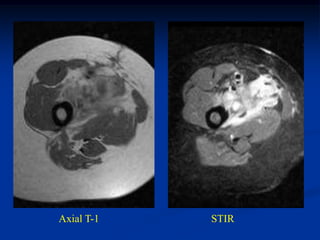

Case #1203.1   Pleomorphic liposarcoma      Axial CT scan

65 year male with recent onset buttock tumor mass in area of previous

resected large benign lipoma 6 years ago

Sag CT scan   Cor CT

Axial T-1     T-2

fluid

tumor

Gad

Sag T-2   Surgical specimen

Case #1203.1 Pleomorphic liposarcoma Axial CT scan 65 year male with recent onset buttock tumor mass in area of previous resected large benign lipoma 6 years ago

Axial T-1 T-2 fluid tumor Gad